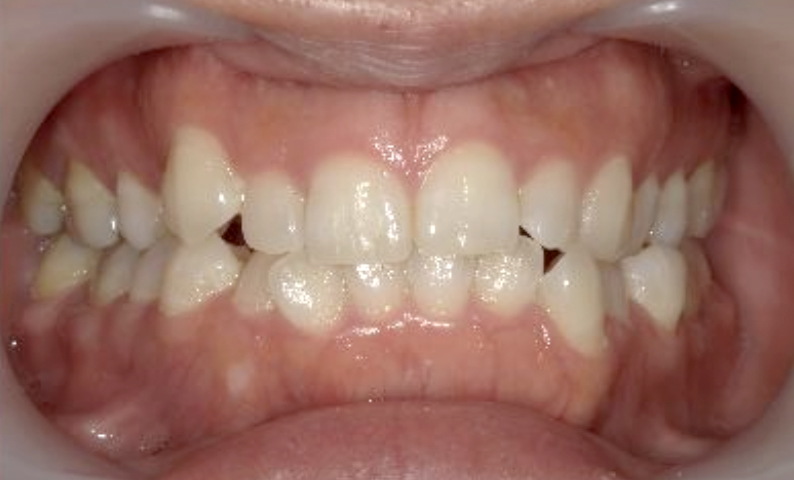

症例_003 下顎だけの部分矯正

治療期間:10ヶ月金額:24万円+税女性前歯のガタガタ下の前歯だけ上顎は補綴治療中

| Before | After |